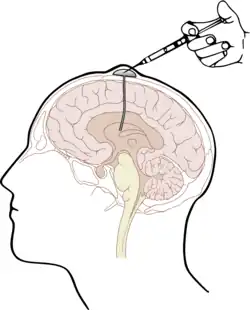

The most widely-used prophylactic drug is methotrexate (MTX), which is normally administered by one of two methods: intravenous injection (IV HD-MTX) and intrathecal injection (IT-MTX).[1][4] Intravenous injection requires a direct injection of high-dose MTX into a patient’s vein;[4] Intrathecal injection, i.e. injection of the drug into the intrathecal space holding cerebrospinal fluid (CSF), is either administered via the Ommaya reservoir, an implanted container passing fluid into the brain, or by lumbar puncture.[1]

The other solution is intrathecal injection of MTX. One method is by surgically implanting under the scalp an Ommaya reservoir, to be attached to a ventricular catheter leading into the ipsilateral anterior horn. The implant provides long-term access to the cerebrospinal fluid and is used for administration of antimicrobials, antifungals, antineoplastic and analgesic medications.[11] Alternatively, MTX may be injected into the intrathecal space via lumbar puncture. After sterilization and local anesthetic, or general anesthesia in paediatric practice, a needle is used to inject MTX between the L3 and L4 or L4 and L5 vertebrae to avoid damage to the conus medullaris.[12]